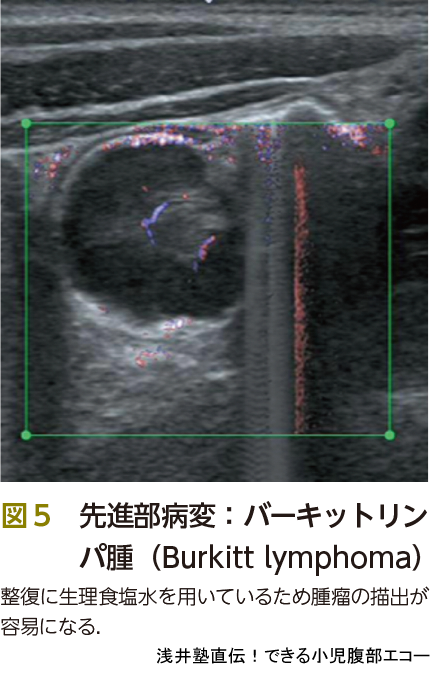

腸重積症はほとんどが小腸が大腸に嵌入する小腸大腸型ですが,小腸が小腸に嵌入する小腸小腸,大腸が大腸に嵌入する大腸大腸型もまれにあります.診断が遅れると腸管壊死に至るので注意が必要です.三主徴は間欠的腹痛,嘔吐,血便ですが,すべてそろう場合は10~50%といわれています2).つまり少しでも鑑別にあがるときにはエコーが重要です.また,先進部に器質的疾患を有する場合もあります.その検索にもエコーは有用です(図4,5).

最後に紛らわしいもの,経過観察でいいもの(いわゆる,もどき)をピットフォールで記載いたしますので参照下さい(図6,7,ピットフォール②).

●整復

場所は蘇生カート,酸素投与,十分なモニターが可能である救急外来で行います.透視室で急変したらたいへんです.被曝をしないことに加えて,場所を問わない,これもエコー整復のメリットです.静脈路確保の後,エコー担当の医師,鎮静・鎮痛・気道管理を行う医師の2人以上で行います.医師が1人しかいない場合の自家麻酔はリスクが上がるので避けるべきですが,医師が2人以上かつ鎮静スキルを有しているならばできるだけ鎮静・鎮痛を行ってもいいのでは,と考えます.この整復術は非常に苦痛と恐怖を伴います.鎮静をかけると児の状態評価が難しい! と思う方もいるかもしれませんが,整復中の状態悪化は穿孔によるものです.エコーを使用していると,腹水の貯留や生理食塩水の滴下速度をみることで穿孔の有無が即座に判断可能です.また体動もないのでモニタリングが容易ですし,整復率があがる報告もあります.医師のスキルしだいで児に苦痛や恐怖を与えるかどうか? 保護者に大絶叫をきかせてしまうか? 大事な課題です.また,記録や介助のため看護師1~2名も同席します(図8).

被曝がない,場所を問わない,生理食塩水を注入するために先進部病変の発見が容易になる,穿孔の際に発見が容易…,などいろいろなメリットがあるエコー整復ですが,いまだに浸透していないのが現状です.その理由の1つとして,整復の瞬間を見落とすことが怖いという意見がありました.これは大丈夫です.見落としても整復後のサイン(図11)を確認すれば,その証明になります.重積部が通過した後の肥厚したバウヒン弁は,カニの爪という意味でcrab-claw signとよばれていますが,私は勝手に「勝利のピースサイン」とよんでいます(図11A).また,整復後の肥厚した回腸末端の短軸像をpost-reduction doughnut signとよびます(図11C).生理食塩水で充満した小腸はhoneycomb sign(図11D)とよばれ,重積が解除されてそこまで生理食塩水が到達したことを示します.小腸小腸重積が残存している場合もあるため,最後のhoneycomb signは重要です.また,バウヒン弁を通過する生理食塩水の勢いも口側に小腸小腸重積,つまり通過障害があるかどうかを判断する情報になります.